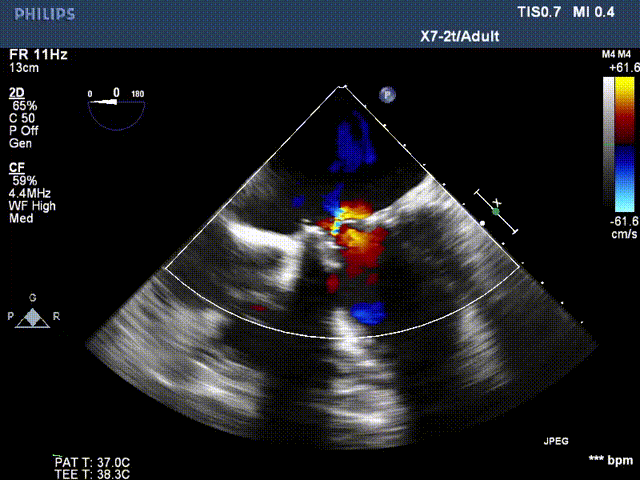

术前超声:

长轴切面二尖瓣狭窄伴关闭不全